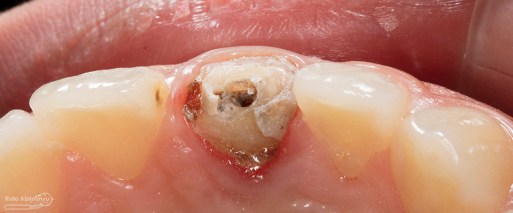

Kondisi setelah crown dibongkar

Kondisi setelah pasak berhasil dikeluarkan

Saya lanjutkan untuk mengeluarkan guttap yang ada di saluran akar, gigi saya isolasi menggunakan rubber dam dan pengeluaran guttap hanya memakai headstroem saja karena guttap tersebut seperti melayang di dalam saluran akar.

Foto klinis setelah proses cleaning and shaping selesai